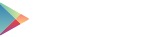

Abb. 1: Akutversorgung Polytrauma; Grenzwertig kardiorespiratorisch stabiler Polytraumapatient (Injury Severity Score: 34) mit Spannungspneumothorax, thorakaler Blutung und weiteren Verletzungen. Primärmaßnahmen: Entlastungspunktion Thorax rechts und Anlage Thoraxdrainage. Bei weiterer thorakaler Blutung, jedoch stabilisierten Verhältnissen, primäre thorakale Versorgung mittels VATS (Videoassistierter Thorakoskopie) und Rippenosteosynthese. A. eingebluteter rechter Lungenunterlappen im WB-CT (schwarzer Pfeil). B. In die Lunge einspießende Rippe (roter Pfeil). C. Durch dislozierte Rippe eingerissener und blutender Lungenunterlappen (gelber Pfeil). D. Abschlussbild mit Rippenosteosynthese (grüner Pfeil).